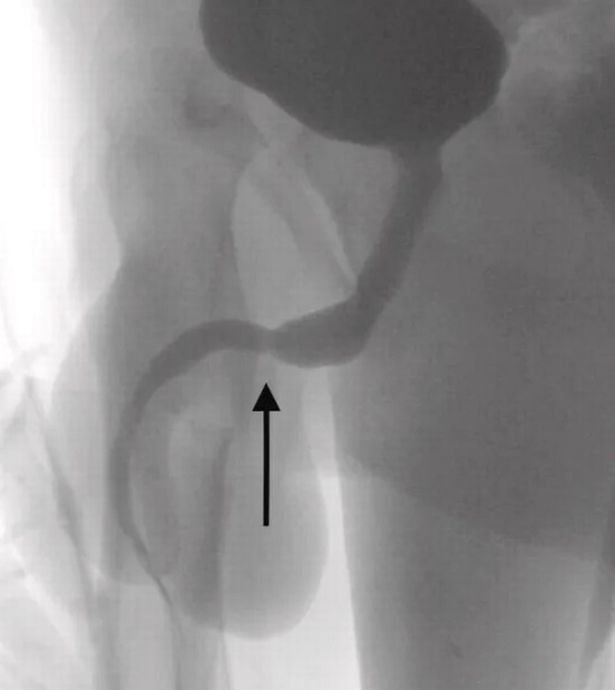

Ameliyatı gerçekleştiren doktorlar durumu kamuoyuna hazırladıkları bir rapor ile duyururken, USB kablolarının vücut içinde düğüm olduğunu ve bu sebeple ameliyatın büyük bir zorluk içerisinde gerçekleştiğini açıkladı.

Science Direct isimli medya platformunun Urology isimli bilimsel dergiden hazırladığı haberde yer alan bilimsel araştırmada olayın 2021’de meydana geldiği belirtildi. Doktorların kaleme aldığı bilimsel araştırmada, “Vücuda yerleştirilen cisim derin doku üzerinden çıkarıldı. Kablolar penis ucundan çıkarıldı” denilirken ismi açıklanmayan gencin cinsel deney için bunu yaptığı ve herhangi bir zihinsel rahatsızlığı olmadığı da duyuruldu